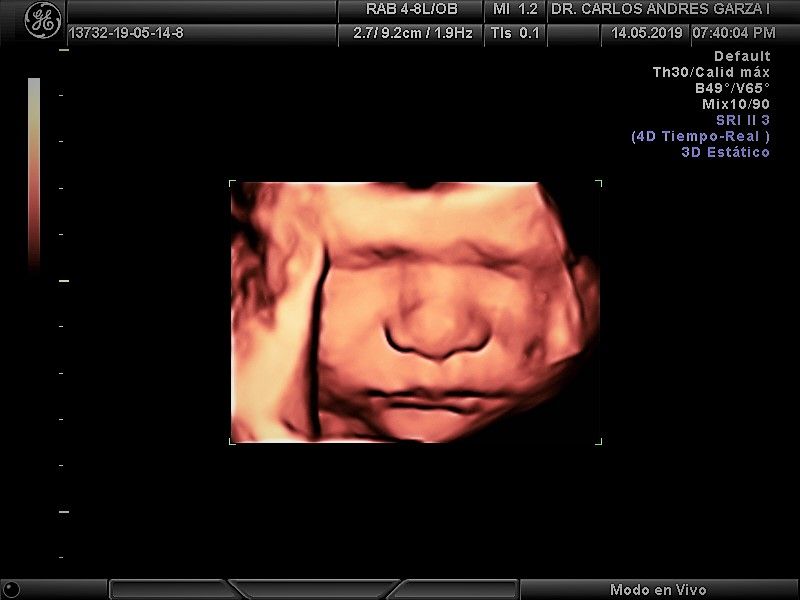

-Sin duda algo que me apasiona es ver la creación mas perfecta que hay sobre la Tierra, que es el desarrollo de un embarazo. Mujeres que están  en una de las  mejores etapas de su vida, en estas consultas  se te hace ver la importancia de un adecuado control prenatal para obtener  el resultado final que es un bebé y una mamá sanos, además realizo ultrasonido 3D y 4D.

Ultrasonido 4D

!Conoce a tu bebé hoy¡ Se trata de la última tecnología en ecografía o ultrasonido a nivel mundial, que consiste en un procesamiento de reconstrucción digital de imágenes para formar una sola imagen en 4 dimensiones, permitiendo así poder visualizar cualquier estructura tal cual la estuviésemos viendo directamente el rostro de tu bebé, antes de nacer. Con esta nueva generación de tecnología del ultrasonido puedes observar datos mas detallados de su bebé, sus movimientos, gestos, risas, bostezo, etc... tal como si lo tuviera en sus brazos. En el pasado los papas no conocían la cara de su bebe hasta que naciera.

Asistencia y control al parto

Llevamos el control de tu embarazo hasta el término del mismo, con la mejor tecnología en cuanto se refiere al ultrasonido 4D, que nos permite revisar de una mejor manera a tu bebé, atendiendo parto o cesárea en los hospitales de la región.